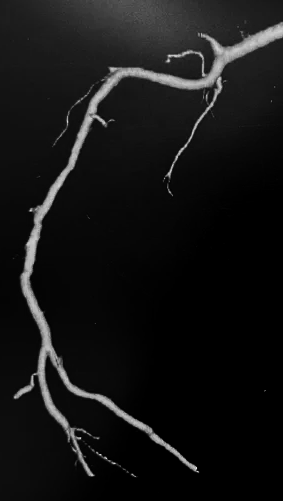

患者为一名老年女性,因高能量撞击导致右上肢开放性肱骨中段骨折,伴随肘部中段大面积皮肤撕裂、肌肉挫伤及血管神经损伤。由当地医院转入九江学院附属医院治疗,入院时创面污染严重,桡动脉搏动消失,肢体远端感觉和血运消失,存在明显出血和神经功能障碍。如处理不当,患者极有可能出现肢体坏死,导致截肢。

九江学院附属医院接诊后立即开通创伤绿色通道进行抢救治疗,完善血管造影检查提示肱动脉栓塞。根据患者骨折类型、软组织损伤程度及全身状况,同时和患者家属进行充分沟通,团队最终确定“右肘皮肤脱套清创+肱骨开放性骨折复位内固定+肱动脉血管、桡神经修复术”,一期保肢,待肢体存活病情稳定后,再行二期创面修复、骨折内固定的阶梯式治疗策略,由黄细高医师主刀,在显微镜下精准吻合断裂的血管神经肌腱,同时采用外固定架对骨折端进行稳定固定。

术后,患者桡动脉搏动强劲有力、手部末梢血运良好,未出现缺血性坏死等严重并发症,病情稳定后,二期行皮肤脱套植皮、骨折内固定治疗,并在康复医学科指导下进行肩肘关节被动活动训练。现患者已康复出院,并送锦旗表示感谢。